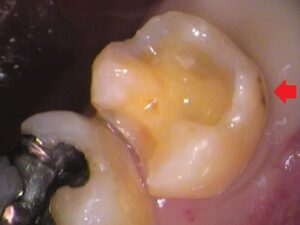

一か所気になる所が。

ココですね。

歯の外側なのですが、黒く虫歯の存在があります。

残してしまって、あとでここから虫歯が進行してしまっては困ります。

虫歯は取り除き、

歯の薄くなってしまっている所も整え、

セラミックが入るように形を整えました。

患者さんのご希望も考慮し、

なるべく最小限の範囲で治療を済ませます。